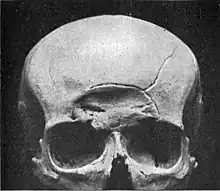

Depressed

A depressed skull fracture is a type of fracture usually resulting from blunt force trauma, such as getting struck with a hammer, rock or getting kicked in the head. These types of fractures—which occur in 11% of severe head injuries—are comminuted fractures in which broken bones displace inward. Depressed skull fractures present a high risk of increased pressure on the brain, or a hemorrhage to the brain that crushes the delicate tissue.

Compound depressed skull fractures occur when there is a laceration over the fracture, putting the internal cranial cavity in contact with the outside environment, increasing the risk of contamination and infection. In complex depressed fractures, the dura mater is torn. Depressed skull fractures may require surgery to lift the bones off the brain if they are pressing on it by making burr holes on the adjacent normal skull.[3]